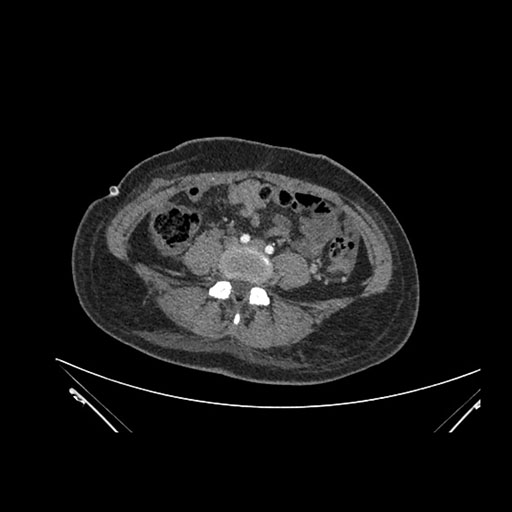

Axial Venous

Imaging analysis

Based on initial findings, which issue(s) would you be most concerned about?